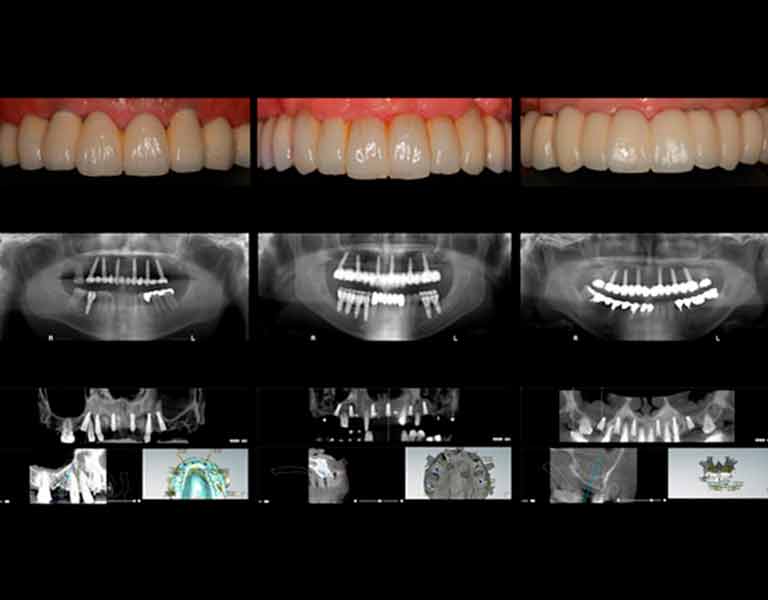

そして、インプラント治療のナビゲーションシステムと言えるシステムが「デジタルインプラント」です。

本書において、この「デジタルインプラント」とはどのようなものか?

そして今までのインプラント治療とどう違うのか?をお話していきたいと思います。